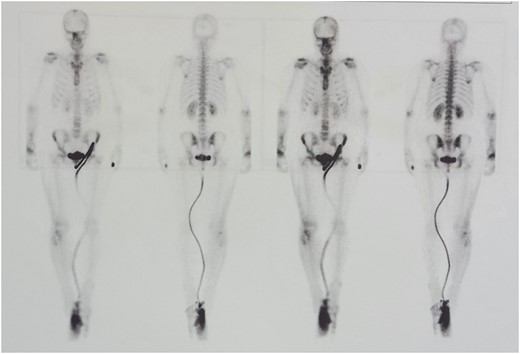

We performed two bone scans, one before and one after the surgical intervention, using 99mTc-MDP as a bone-seeking agent. A preoperative bone scan revealed increased pathologic accumulation of the bone-seeking radiotracer on the late static images in the right distal radius, conclusive with the localization of the GTC. The postoperative bone scan with SPECT/CT study, one month after the surgical procedure, detected diffuse emphasized blood pool phase as well as an increased accumulation of the tracer in the right distal radius, which corresponded to the viable vascular graft implanted (Figs 5 and 6).